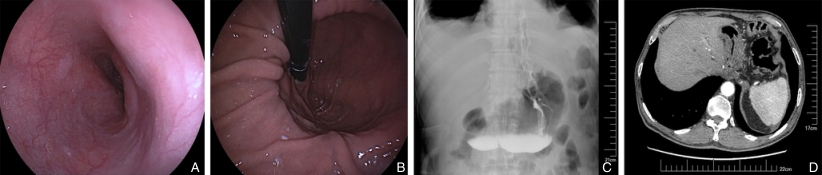

图2 1例单肌瓣吻合术后患者复查内镜及影像 A:食管下端;B:倒镜下吻合口及新胃底;C:上消化道碘剂造影;D:增强CT食管下端与胃壁Fig.2 Follow-up endoscopy and imaging of a patient after single-flap anastomosis A: Lower end of the esophagus; B: Anastomosis site and new gastric fundus observed with retroflexed endoscopy; C: Upper gastrointestinal iodine contrast imaging; D: Enhanced CT showing the lower esophagus and gastric wall